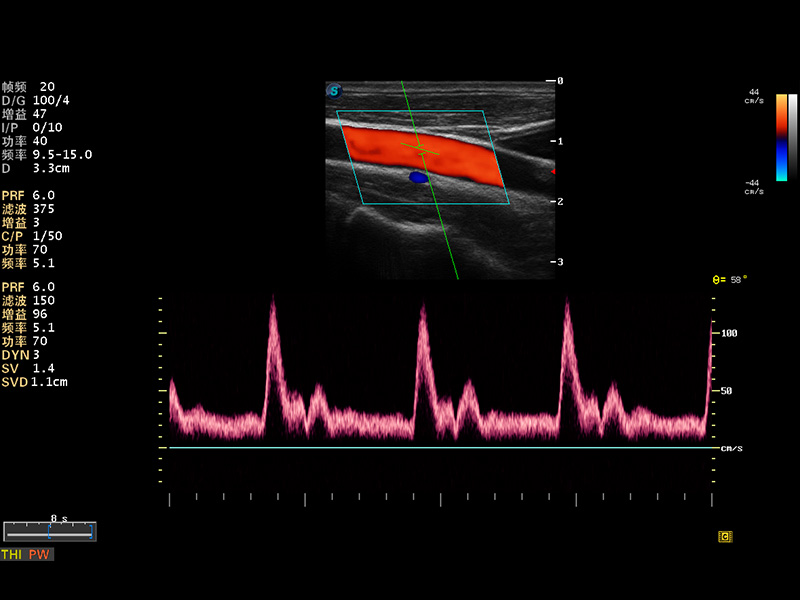

S8 EXP便携式彩色多普勒超声诊断仪是竞技宝(JJB)官方网站研发的高端全身应用型便携彩超。高通道的VIS平台融合可视化(Visual)、智能化(Intelligent)和人性化(Smart)的特点,配以竞技宝(JJB)官方网站自主研发生产的探头大家族,使您能够快速、准确的获得病人信息,提高工作效率的同时减轻疲劳。

成像技术

多波束形成器